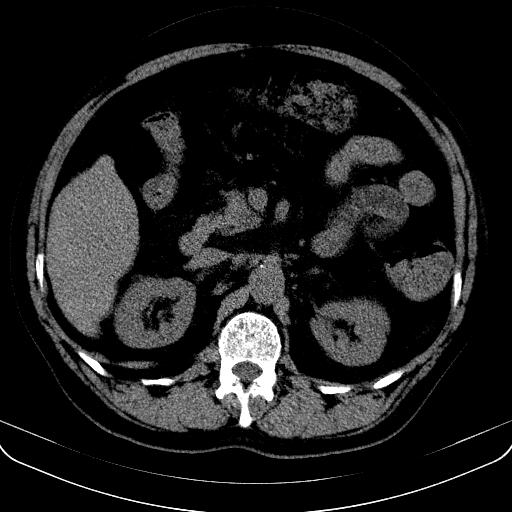

以下是引用jia119在2008-3-5 13:31:00的发言:[br]肝内多发片状低密度影,密度不均,我还是考虑肝ca可能,另肝内小囊肿,胆囊增大。

以下是引用形影不离在2008-3-5 12:18:00的发言:[br]肝硬化伴门脉高压征,肝内占位待排,增强再说.

以下是引用随光逐影在2008-3-5 21:11:00的发言:[br]肝硬化伴门脉高压(食管下段静脉曲张),肝癌不排除。建议:行ct增强扫描检查。

以下是引用同在2008-3-5 13:56:00的发言:[br]考虑肝癌可能性大,胆囊增大.